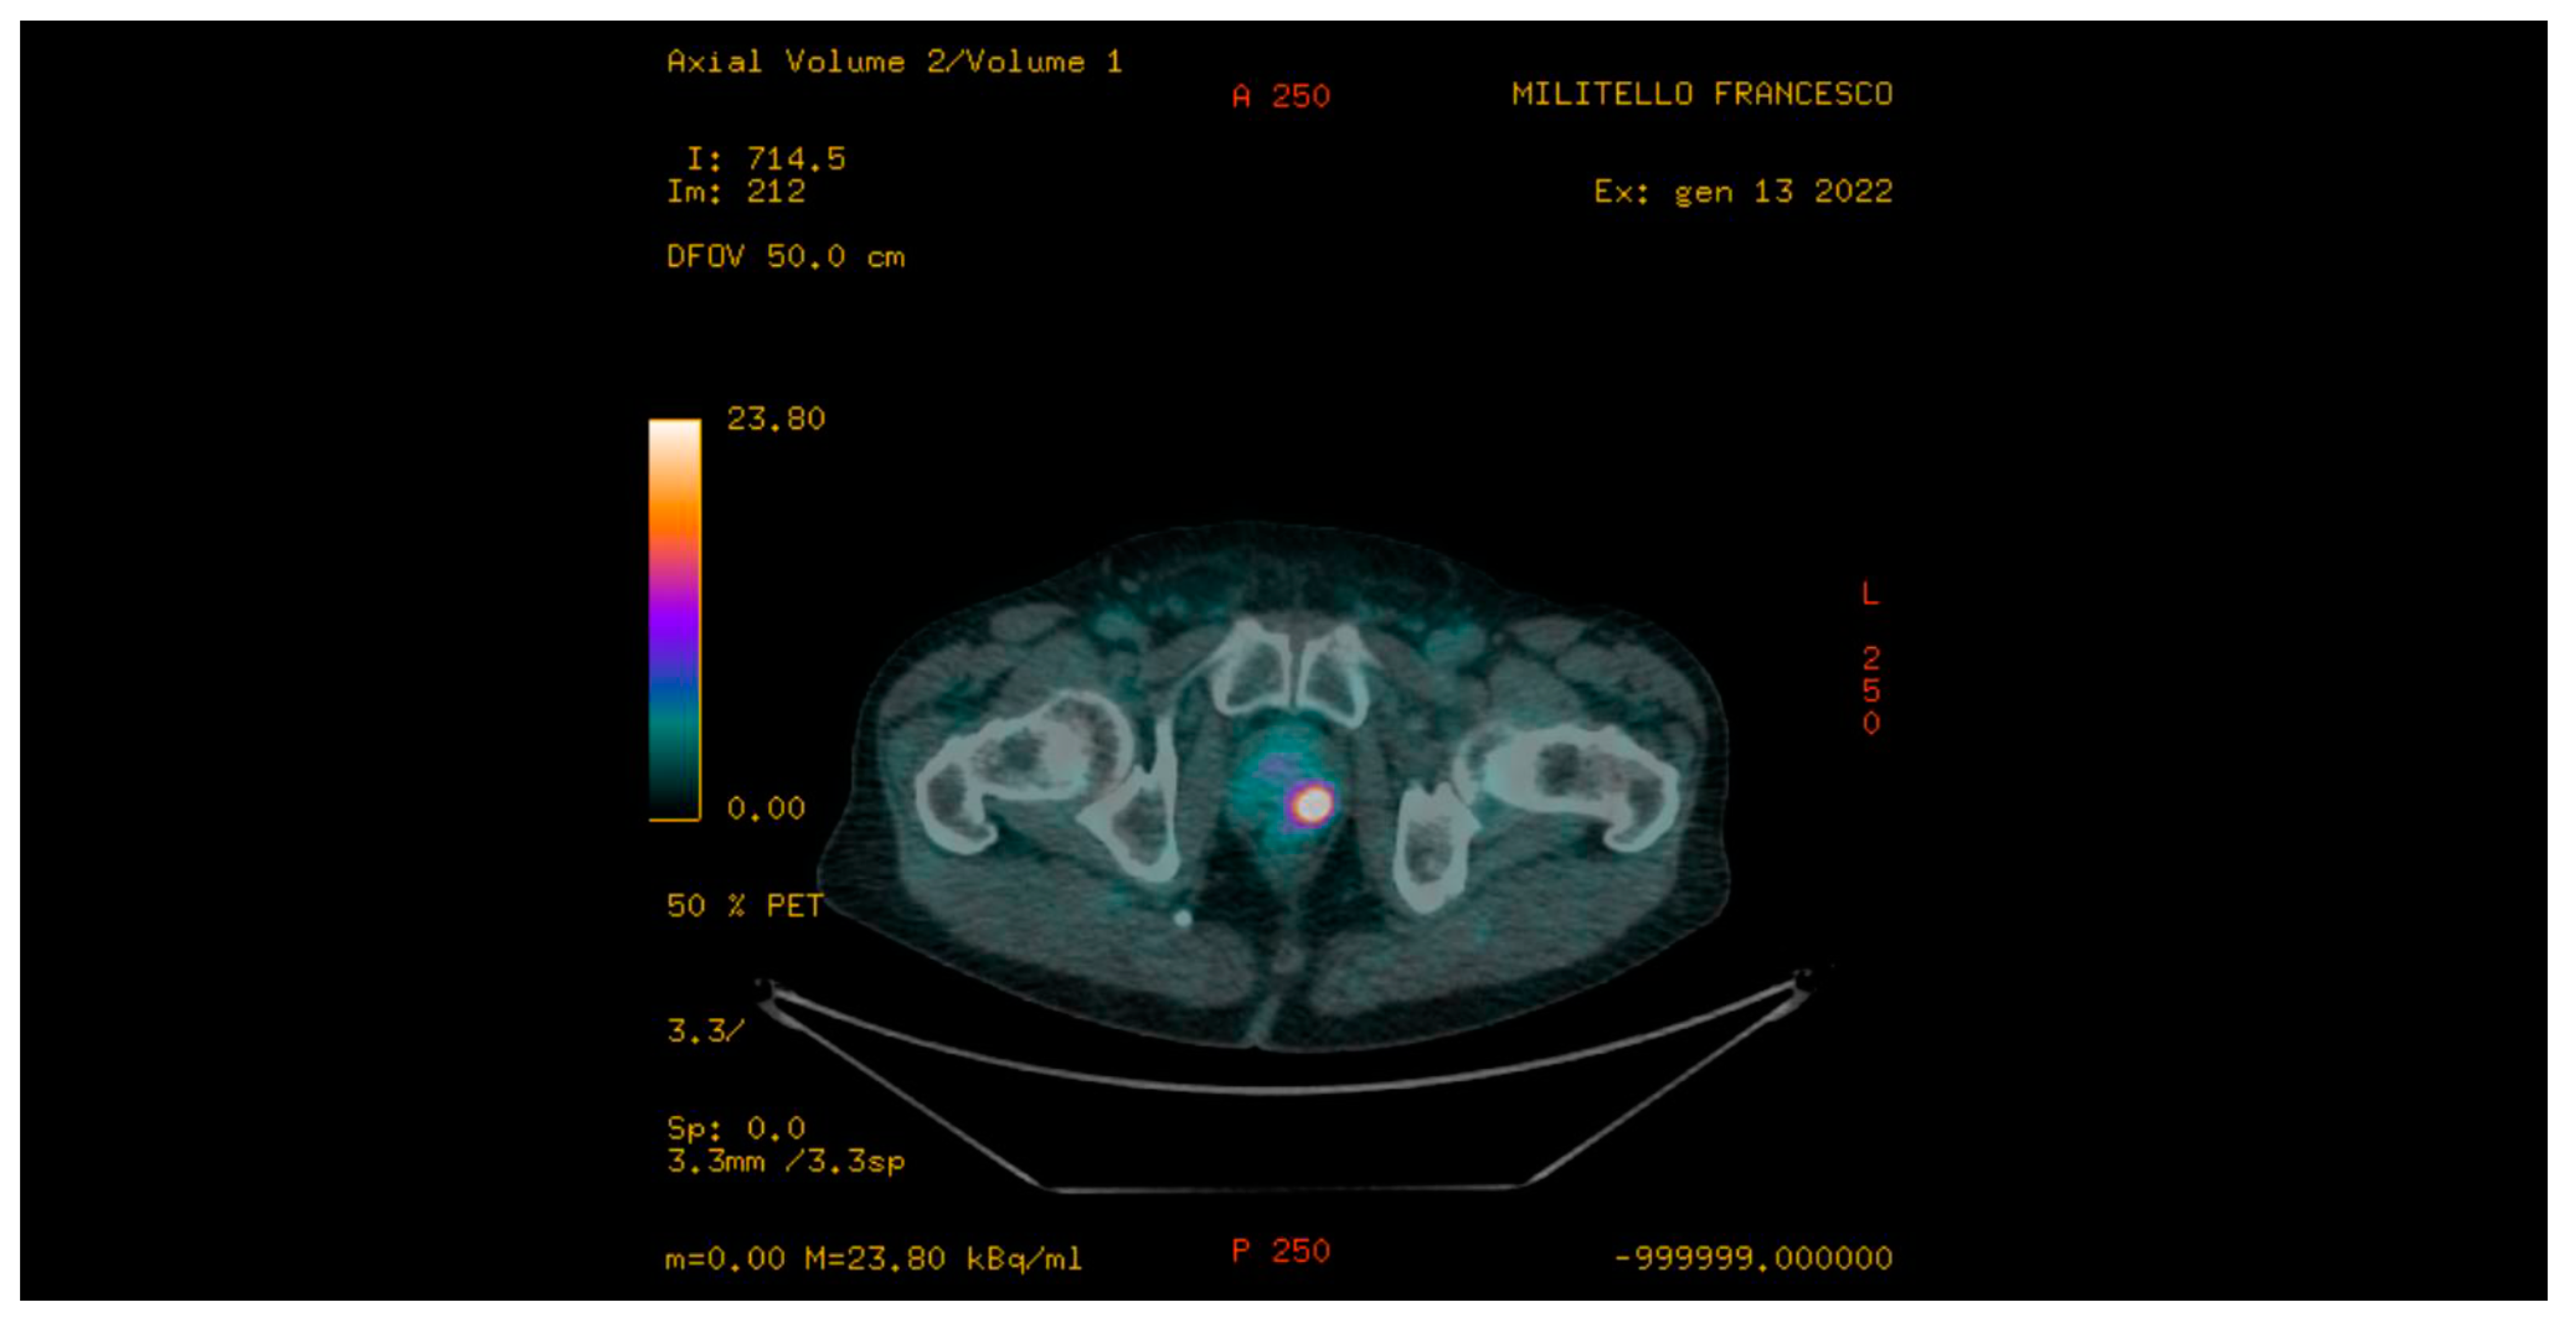

| 68Ga-PSMA PET/CT suspicious for PCa | 6 (20%) |